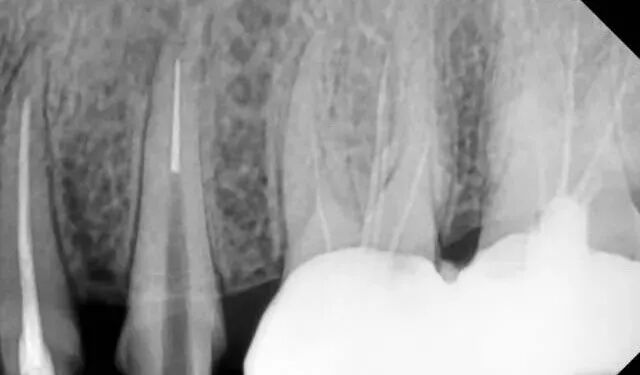

镍钛器械的分离大体上可以分为两种方式,即扭力折断( torsional fracture)和旋转疲劳( cyclic fatigue)折断。

扭力折断是指器械的尖端或任何一部分卡在根管的狭窄处,其柄部仍在旋转,超过镍钛合金的最大弹性形变限度而造成的器械折断。

这种折断多发生于小号器械和器械的尖端,因为小号器械多用于根尖弯曲部位的预备,易被卡住而发生折断。发生扭力折断的器械表面常有可见的变形,如解螺旋、螺纹不规则或反向紧致等。

疲劳折断系金属弯曲疲劳所致,器械在根管内虽未被卡住,但在弯曲部位反复旋转的过程中不断地被拉伸和压缩产生金属疲劳,从而在远小于器械本身弹性极限的情况下折断。此类型的器械折断常常在没有任何征兆的情况下发生,被认为是机用镍钛器械折断的一个重要因素。

器械在根管内的应力与根管的弯曲角度呈正相关,弯曲角度越大,应力越大,器械越容易发生疲劳折断。研究表明机用镍钛器械在预备弯曲度>30°的根管时,则有12.5%的折断率,且均发生在根管的根尖区。

弯曲半径代表根管弯曲的陡峭程度,半径越小,根管就越弯曲。当弯曲半径减小时,器械的应力和扭力增加,疲劳周期缩短,易发生折断。